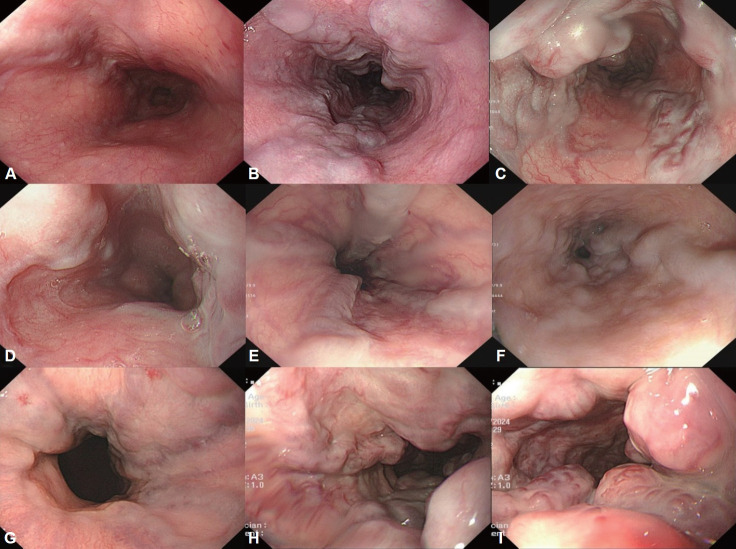

胃食管静脉曲张发生在超过一半的肝硬化患者中,随着肝功能的恶化,发生率增加。尽管随着内窥镜下静脉曲张止血技术的发展以及血管活性药物和预防性抗生素的应用,急性静脉曲张出血的死亡率有所下降,但仍高达20%。因此,对肝硬化患者进行静脉曲张的监测和预防其出血是非常重要的。肝硬化合并门脉高压的患者,应行食管胃十二指肠镜诊断静脉曲张并对其出血风险进行分层。内镜监测间隔根据静脉曲张情况和肝硬化严重程度调整。如果诊断出静脉曲张,则需要一级预防(例如,非选择性β受体阻滞剂或内窥镜预防)来预防静脉曲张出血。急性静脉曲张出血患者应进行适当的治疗,包括及时的内镜止血,并需要二级预防以防止再出血。内镜下静脉曲张结扎是急性食管静脉曲张出血的推荐内镜治疗方法;内镜下静脉曲张梗阻通常推荐用于胃静脉曲张患者。为防止出血,应定期进行内镜监测,直至静脉曲张完全根除,即使静脉曲张消失后也应定期进行内镜随访。在这篇综述中,我们探讨了内镜在胃食管静脉曲张的治疗和管理中的作用。

Gastroesophageal varices occur in more than half of patients with cirrhosis and the incidence increases as liver function worsens. Although the mortality rate for acute variceal bleeding has decreased with the development of variceal endoscopic hemostasis and administration of vasoactive drugs and prophylactic antibiotics, it still reaches 20%. Therefore, surveillance of variceal occurrence and the prevention of their bleeding is very important in patients with cirrhosis. In patients with liver cirrhosis accompanied by portal hypertension, esophagogastroduodenoscopy should be performed to diagnose varices and stratify their bleeding risk. The interval of endoscopic surveillance is adjusted according to variceal condition and cirrhosis severity. If varices are diagnosed, primary prophylaxis (e.g., non-selective beta-blockers or endoscopic prophylaxis) is required to prevent variceal bleeding. Appropriate treatment, including timely endoscopic hemostasis, should be performed in patients with acute variceal bleeding, and secondary prophylaxis is required to prevent rebleeding. Endoscopic variceal ligation is the recommended endoscopic treatment for acute esophageal variceal bleeding; endoscopic variceal obstruction is usually recommended in patients with gastric varices. To prevent bleeding, endoscopic surveillance should be performed at regular intervals until the varices have been eradicated, and endoscopic followup should be performed periodically even after their disappearance. In this review, we investigate the role of endoscopy in the treatment and management of gastroesophageal varices.